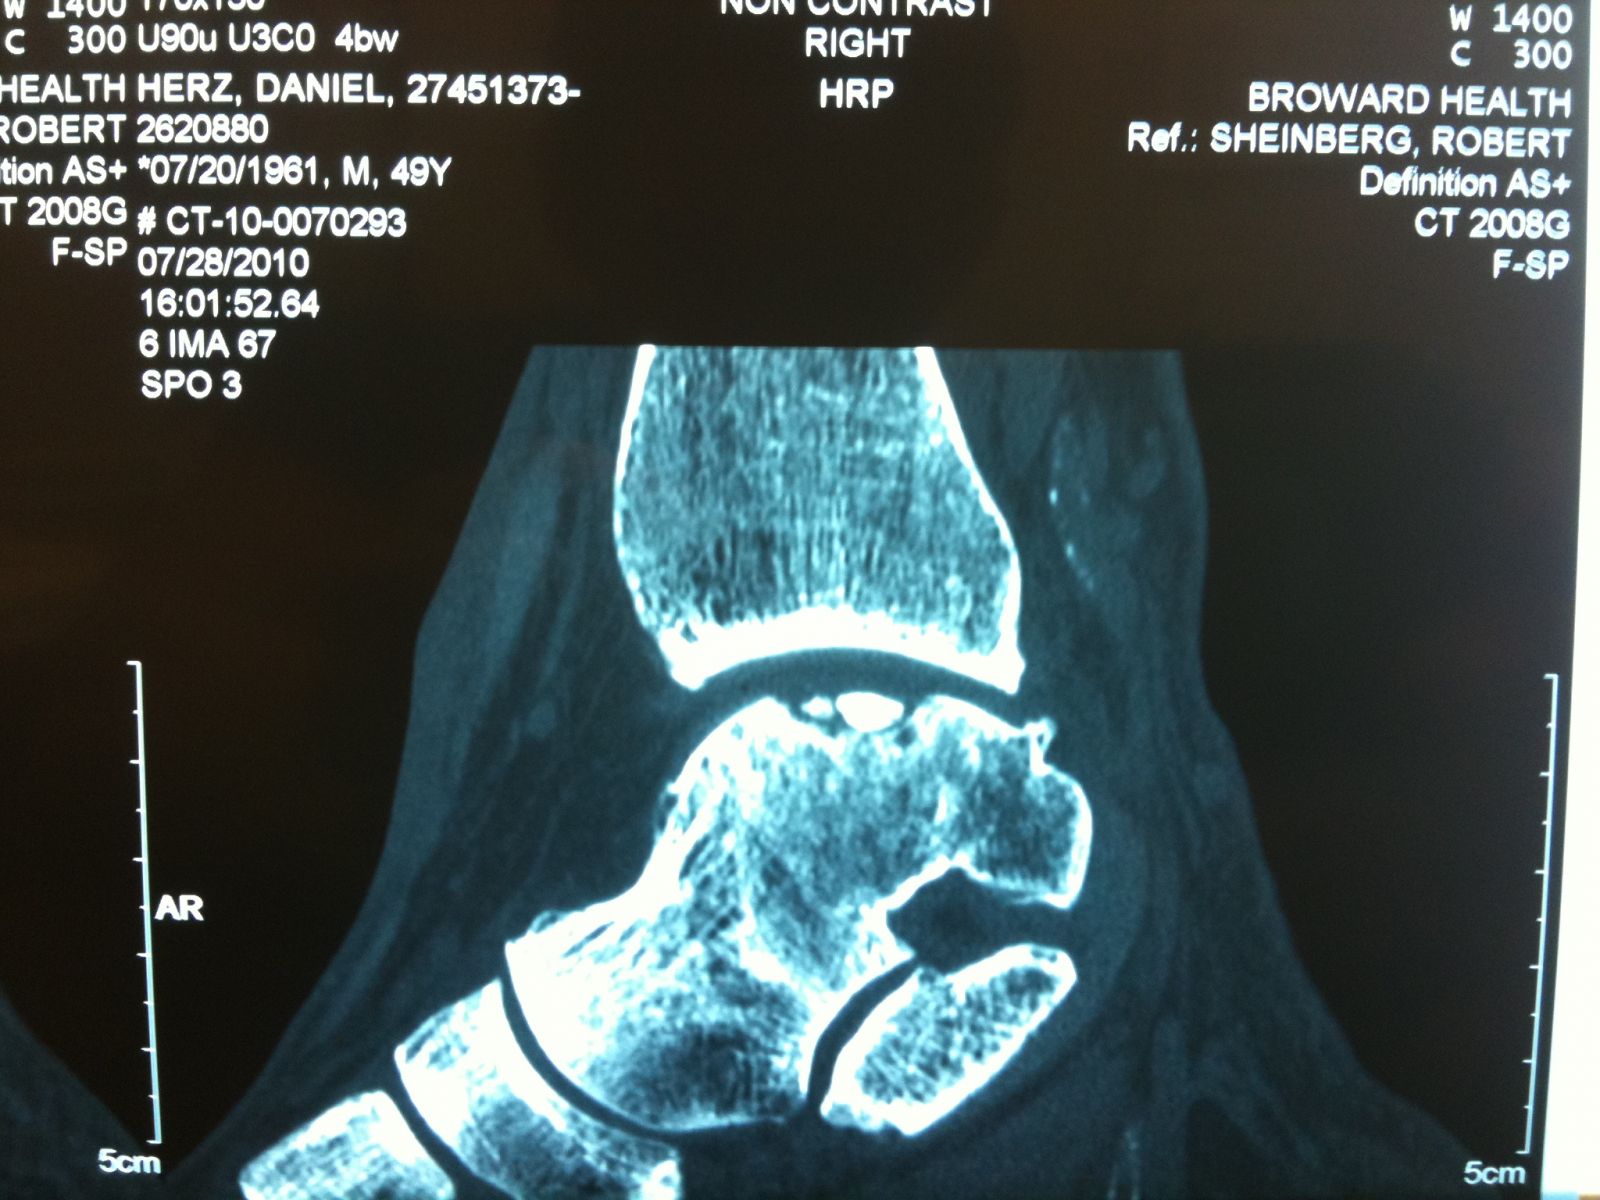

Intraop arthroscopic pics of talar OCD surgery.

A series of intraop ankle arthroscopy pics of synovial chondromatosis with OCD talus and tibia and microfracture.